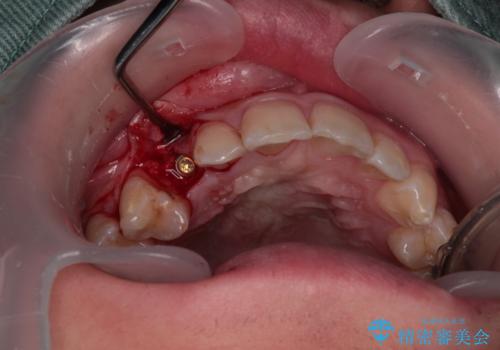

- 永久歯が生えてこず、欠損になっていることを気にして来院された患者様です。

CT撮影を行ったところ、埋もれている犬歯を牽引して萌出させることは不可能と判断し、インプラントによる補綴治療を行うこととしました。

現在では、埋入時に仮歯を装着する「即時荷重インプラント」での取り扱いとなりますが、治療当時は未導入であったため、従来の複数回の外科処置を行う術式で治療を行いました。